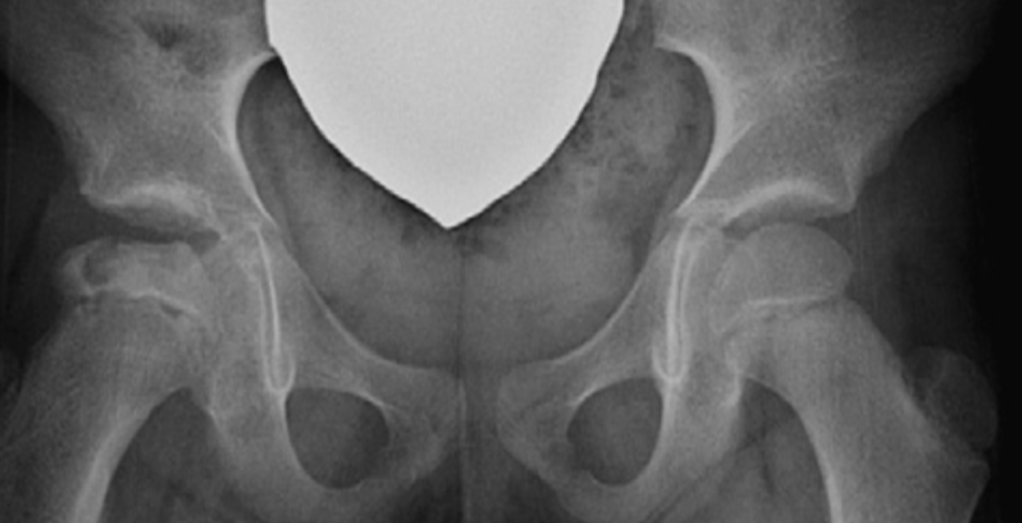

Enfermedad de Legg Calvé Perthes

Eventos repetidos de isquemia que afectan la epífisis femoral proximal, generando cambios en la cabeza femoral. 1